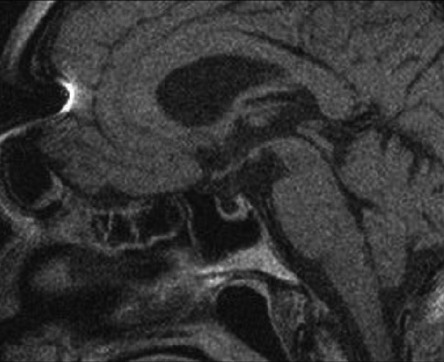

Abstract Image

Acromegaly and gigantism are hormonal disorders which develop as a consequence of chronic growth hormone hypersecretion. The prefix pseudo- is used to describe a certain clinical condition without a clearly proven characteristic of pathophysiological mechanism and basic biochemical features; pseudoacromegaly or acromegaloidism match the definition from above. In this case reports, we will try to provide a concise overview of diagnostic evaluation of acromegaloid physical appearance, while discussing two cases of patients who have similar clinical acromegaloid features as the first sign of the disease but have completely different etiologic backgrounds of their acromegalic appearance. The first case is of a 57-year-old male who presented with a marked acral growth and coarse facial features, but the diagnosis of secondary amyloidosis caused by multiple myeloma was confirmed just after biopsy of tongue and buccal mucosa. The second case is that of a 63-year-old male with an acromegaloid appearance caused by ectopic secretion of GH secreting lung carcinoma. The early diagnosis of ectopic acromegaly and pseudoacromegaly is still a challenging process. The key task is to confirm the GH axis abnormalities and establish the underlying disease, as a crucial step for faster treatment and need to avoid unnecessary therapeutic procedures to decreased mortality and improved quality of life.